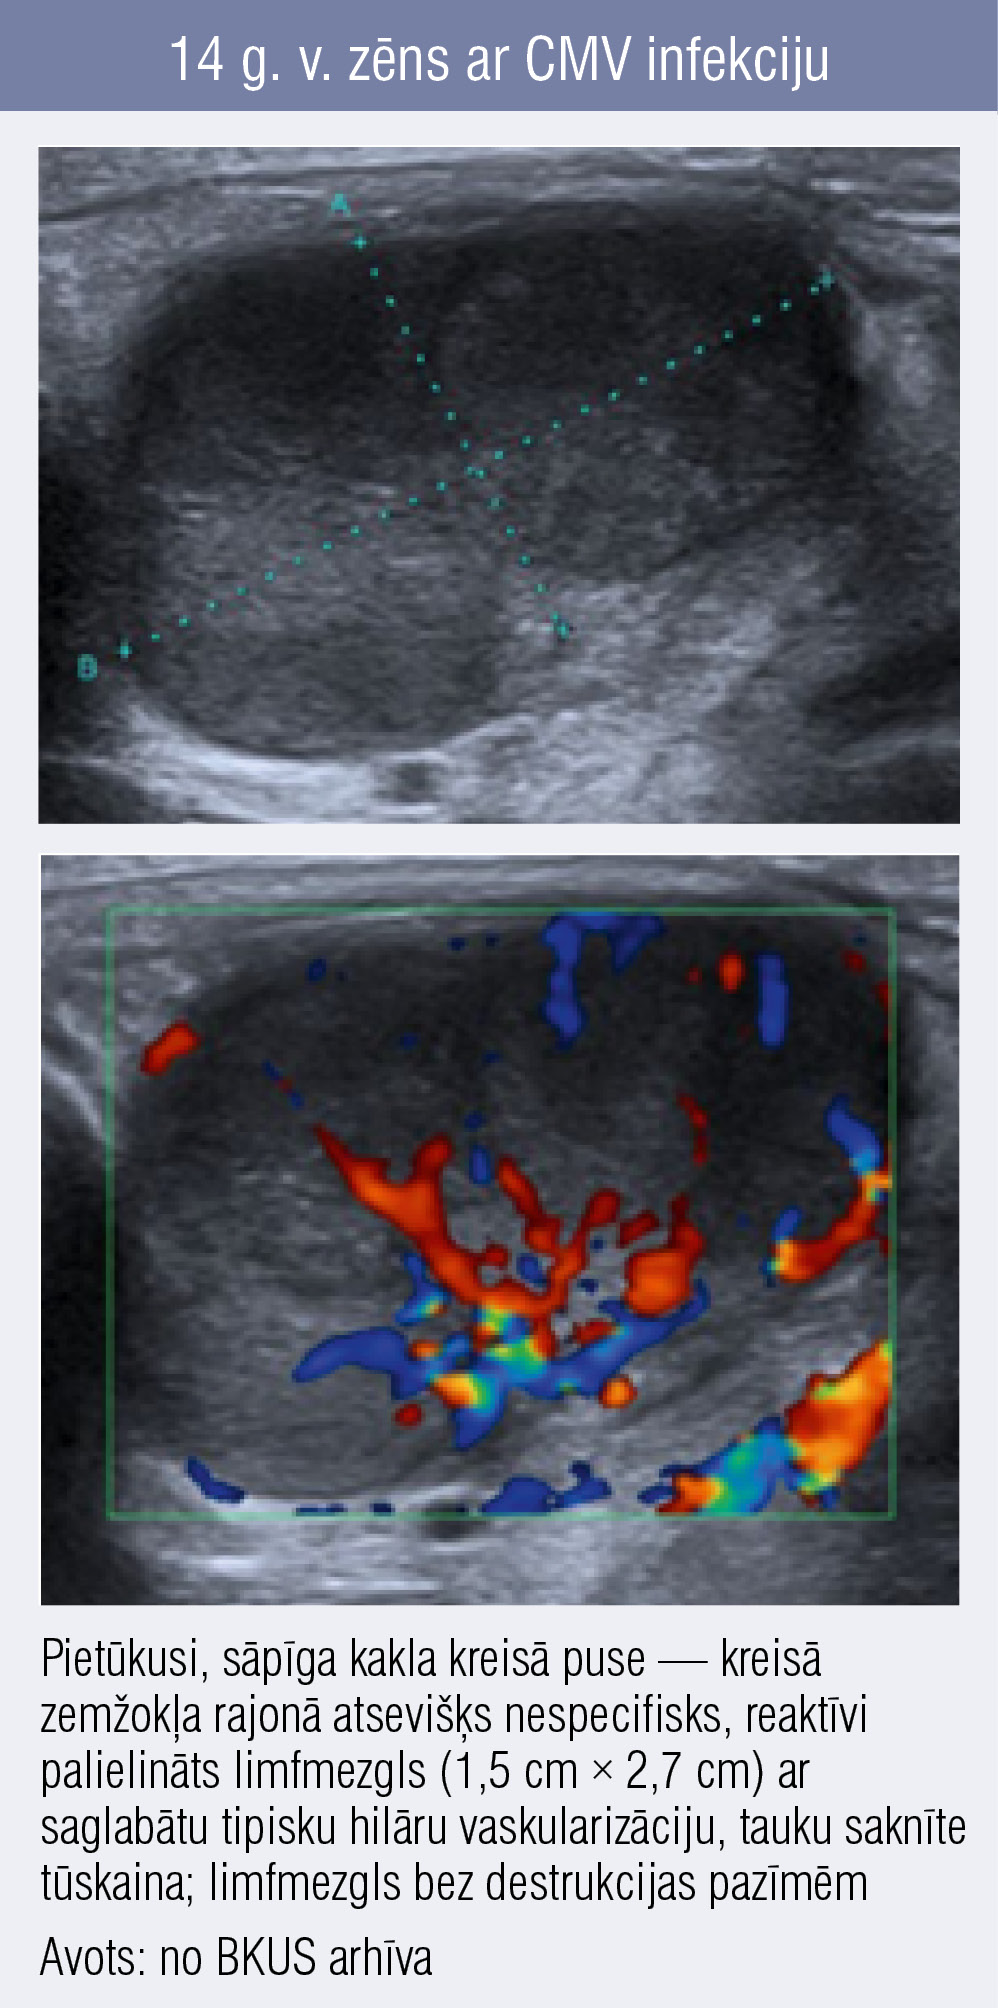

14 g. v. zēns ar CMV infekciju 14 g. v. zēns ar CMV infekciju

14 g. v. zēns ar CMV infekciju

Reaktīvi limfmezgli būs palielināti izmērā, parasti tie saglabā ovālu formu, jo limfoproliferācija notiek difūzi, ultrasonogrāfijā tie būs vizuāli hipoehogēnāki (tumšāki), salīdzinot ar normāliem limfmezgliem, un ar plašāku ehogēno hilu un pastiprinātu hilāru vaskularizāciju. Reaktīva limfadenopātija var radīt diagnostiskas grūtības, jo atsevišķs mezgls var būt nesamērīgi palielināts salīdzinājumā ar pārējiem (2. attēls).